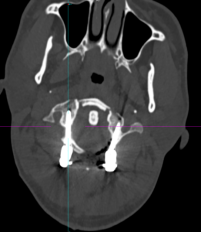

该患者的治疗关键在于两个方面:一是能否将螺钉置入漂浮的寰椎侧块中从而达到骨折的复位及固定?二是该患者同时还伴有双侧枢椎椎弓根先天性发育不良、椎动脉高跨,能否顺利植入椎弓根螺钉?经过为期一周的颅骨牵引和术前准备,杨先生于近日接受了手术。对于此类颈椎手术,经验丰富的姜为民主任早已开展了多年,与以往不同的是这次手术多了一台“GPS”---“O”-臂机,这也是我院首次术中开机实用。

术中“O”-臂机导航图像

在麻醉手术科的配合下,有了高精尖的第二代“O”-臂机的辅助,加之姜主任丰富的临床经验,手术非常顺利。第二代“O”-臂机扫描颈椎三维重建显示寰椎移位的骨块复位完成,寰枢椎椎弓根螺钉位置良好。术后,患者颈部疼痛症状明显改善。